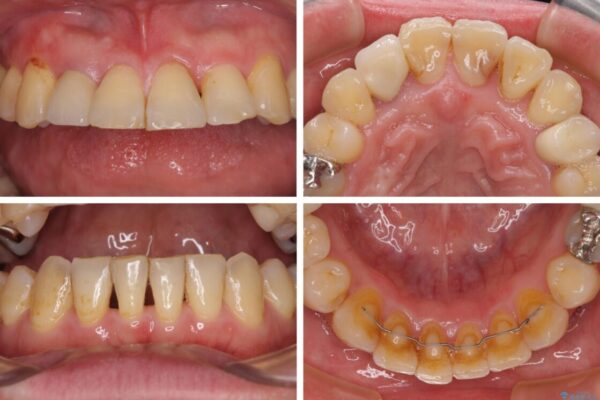

治療後

• 割れてしまった奥歯とデコボコの前歯 矯正治療とインプラント治療 治療後画像